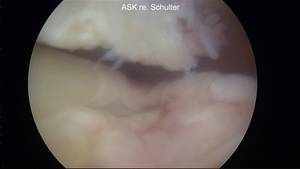

Die Rotatorenmanschette umgreift mit ihren Sehnen den Oberarmkopf und stabilisiert ihn in der Schultergelenkspfanne. Sie besteht aus vier Muskeln, von denen der Supraspinatusmuskel und seine Sehne am häufigsten betroffen sind. Ein Riss der Rotatorenmanschette kann ein subacromiales Impingementsyndrom begleiten oder nach einem Unfall (z.B. Sturz auf den nach hinten ausgestreckten Arm) entstehen. Je nach Größe und Alter der Ruptur ist eine Naht des Risses möglich. Dabei wird die ausgerissene Sehne am Knochen über sog. Fadenanker befestigt. Die Operation kann je nach Lage und Größe arthroskopisch oder offen („mini-open“) durchgeführt werden. Unabhängig vom Operationsverfahren ist eine sechswöchige Ruhigstellung nach der Operation erforderlich, um die Einheilung der Sehne an den Knochen zu ermöglichen.